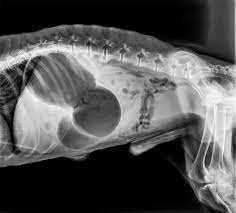

Dogs suffering from bloat may have a swollen or enlarged stomach which may or may not be visible just by looking at your dog. Directions for passing stomach tube. Simethicone is used to relieve gas and bloating in human products.